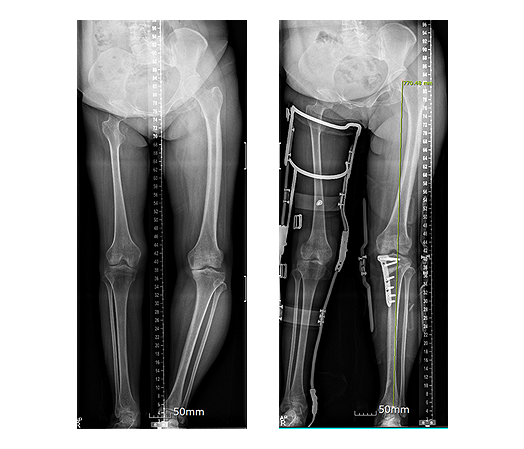

절골술

- 하지의 비정상적인 축을 바로잡음으로써 퇴행성 변화가 심한 구획에 가해지는 체중 부하를 줄이면서 부하의 일부를 비교적 건강한 과절면으로 옮겨 통증을 감소시키는 술식

Indication

- 60세 미만의 비만하지 않은 환자

- 내반슬의 변형과 내측 경대퇴 관절면만의 병변이 있거나, 외반슬의 변형과 동반하여 외측 관절면만의 병변이 있는 경우

- 안정성에 문제가 없고, 슬개-대퇴관절은 정상

- 완전 신전과 90도 이상의 굴곡 가능

ContraIndication

- 미만성, 비특징적 통증, 20도 이상의 교정 필요한 경우, 15도 이상 굴곡구축

개방성 설상 근위 경골 절골술